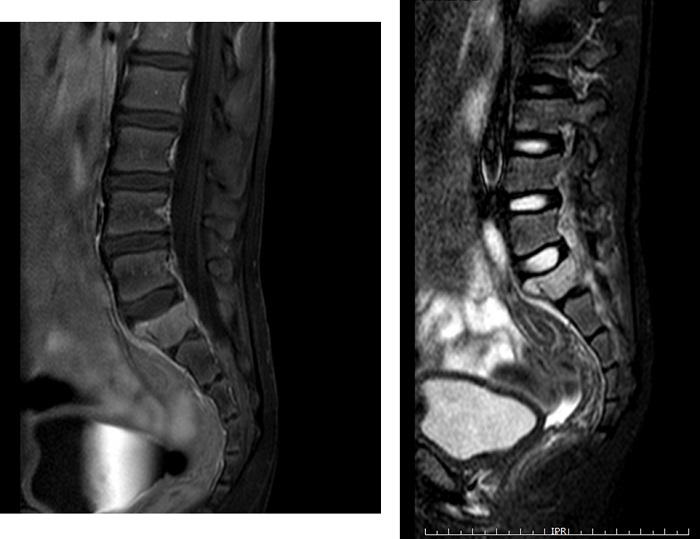

En la RM realizada se observa una lesión lítica expansiva en el ala derecha de S1, junto con un aumento de partes blandas (Fig. 1), por lo que se necesita realizar una biopsia para completar estudio. Se obtuvo muestra con diagnóstico de HCL. Dado que en ese momento presentaba afectación de un único hueso, se decidió adoptar una actitud expectante.

| Figura 1. Diferentes secuencias de RM lumbar y sacro-iliaca. Se identifica lesión lítica expansiva en ala sacra derecha y cuerpo de S1, asociando pequeña masa de partes blandas y disminución de la altura/aplastamiento del cuerpo de S1 con hundimiento de la cortical superior con disco intervertebral L5-S1 ensanchado, ocupando la depresión ósea |